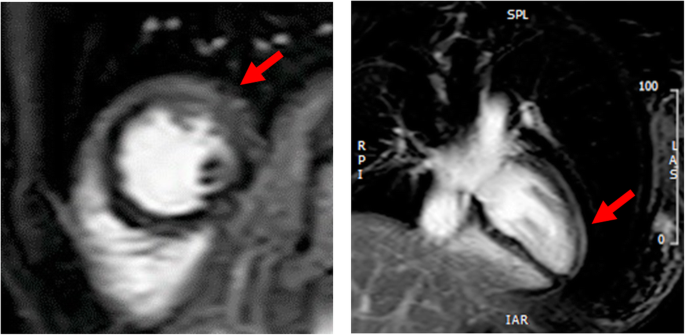

Although serum amylase (1800 U/L, Fig. 2), lipase and trypsin (320 U/L and 3040 ng/mL respectively) were elevated, reexamination with CT scanning (Fig. 1b) showed amelioration of the pancreatic swelling and magnetic resonance cholangiopancreatography (MRCP) imaging depicted no abnormalities, even in the pancreas (data not shown). On the second day in our hospital, her symptoms showed improvement, and the serum glucose level had fallen below 200 mg/dL. However, on the 3rd hospital day, electrocardiography (ECG) depicted ST-segment elevation in V3-V6 (Fig. 3) without typical cardiac symptoms but serum creatinine kinase (CK) (830 U/L, Fig. 2), CK-MB and troponin I (49 U/L and 11.99 ng/mL respectively) were elevated. Coronary angiography showed no abnormal findings. Left ventriculography (LVG) showed apical wall hypokinesis, while no other abnormal findings, including takotsubo cardiomyopathy, were detected. On the 4th hospital day, abnormal ECG findings showed improvement and serum myocardial necrosis markers had normalized. On the 8th hospital day, contrast-enhanced cardiac magnetic resonance imaging (MRI) indicated late gadolinium enhancement (LGE) in the apical wall (Fig. 4). She was diagnosed with acute myocarditis based on the guidelines for diagnosis of myocarditis [9]. It should be noted that no abnormality was observed in echocardiogram examination and that serum CK level was 156 U/L at the previous hospital. On the 28th hospital day, follow-up cardiac MRI showed no LGE in the apical wall.